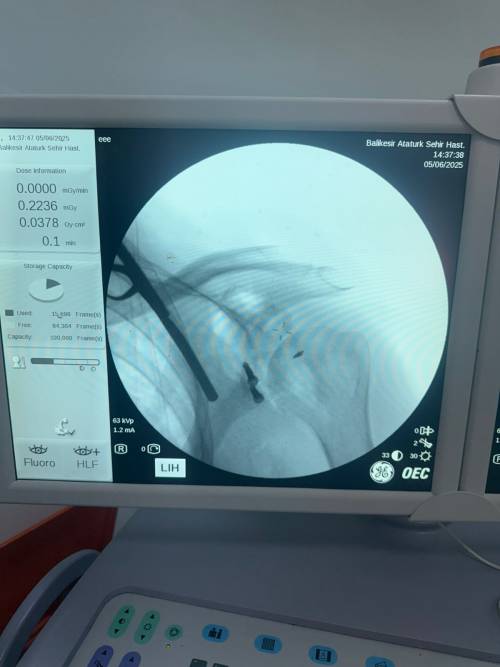

Daha önceden yaklaşık on beş defa omuzu çıkan ve başka İllerde (İzmir-İstanbul ) Özel Hastanelerde üç defa ameliyat olan hasta şikayetlerinin geçmemesi ve omuzunun tekrar çıkması üzerine Balıkesir Atatürk Şehir Hastanesi Ortopedi ve Travmatoloji Kliniğine başvurdu. Hastanın yapılan muayenesi ve tetkikleri sonucu, hastanın omuz ekleminde aşırı kemik dokusu kaybı mevcut olması sebebiyle “Latarjet omuz ameliyatı” planlandı. Balıkesir de ilk defa uygulanan bu yöntem Doç. Dr. Özgün Karakuş ve Op. Dr. Fatih Işık tarafından başarıyla gerçekleştirildi. Ameliyat sonrası sağlığına kavuşan hasta bir gün sonra taburcu edildi.